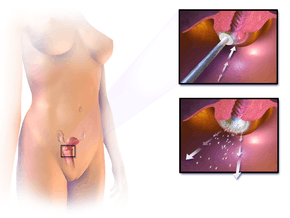

Treatment for higher grade CIN involves removal or destruction of the neoplastic cervical cells by cryocautery, electrocautery, laser cautery, loop electrical excision procedure (LEEP), or cervical conization. Therapeutic vaccines are currently undergoing clinical trials. The lifetime recurrence rate of CIN is about 20%, but it isn't clear what proportion of these cases are new infections rather than recurrences of the original infection.